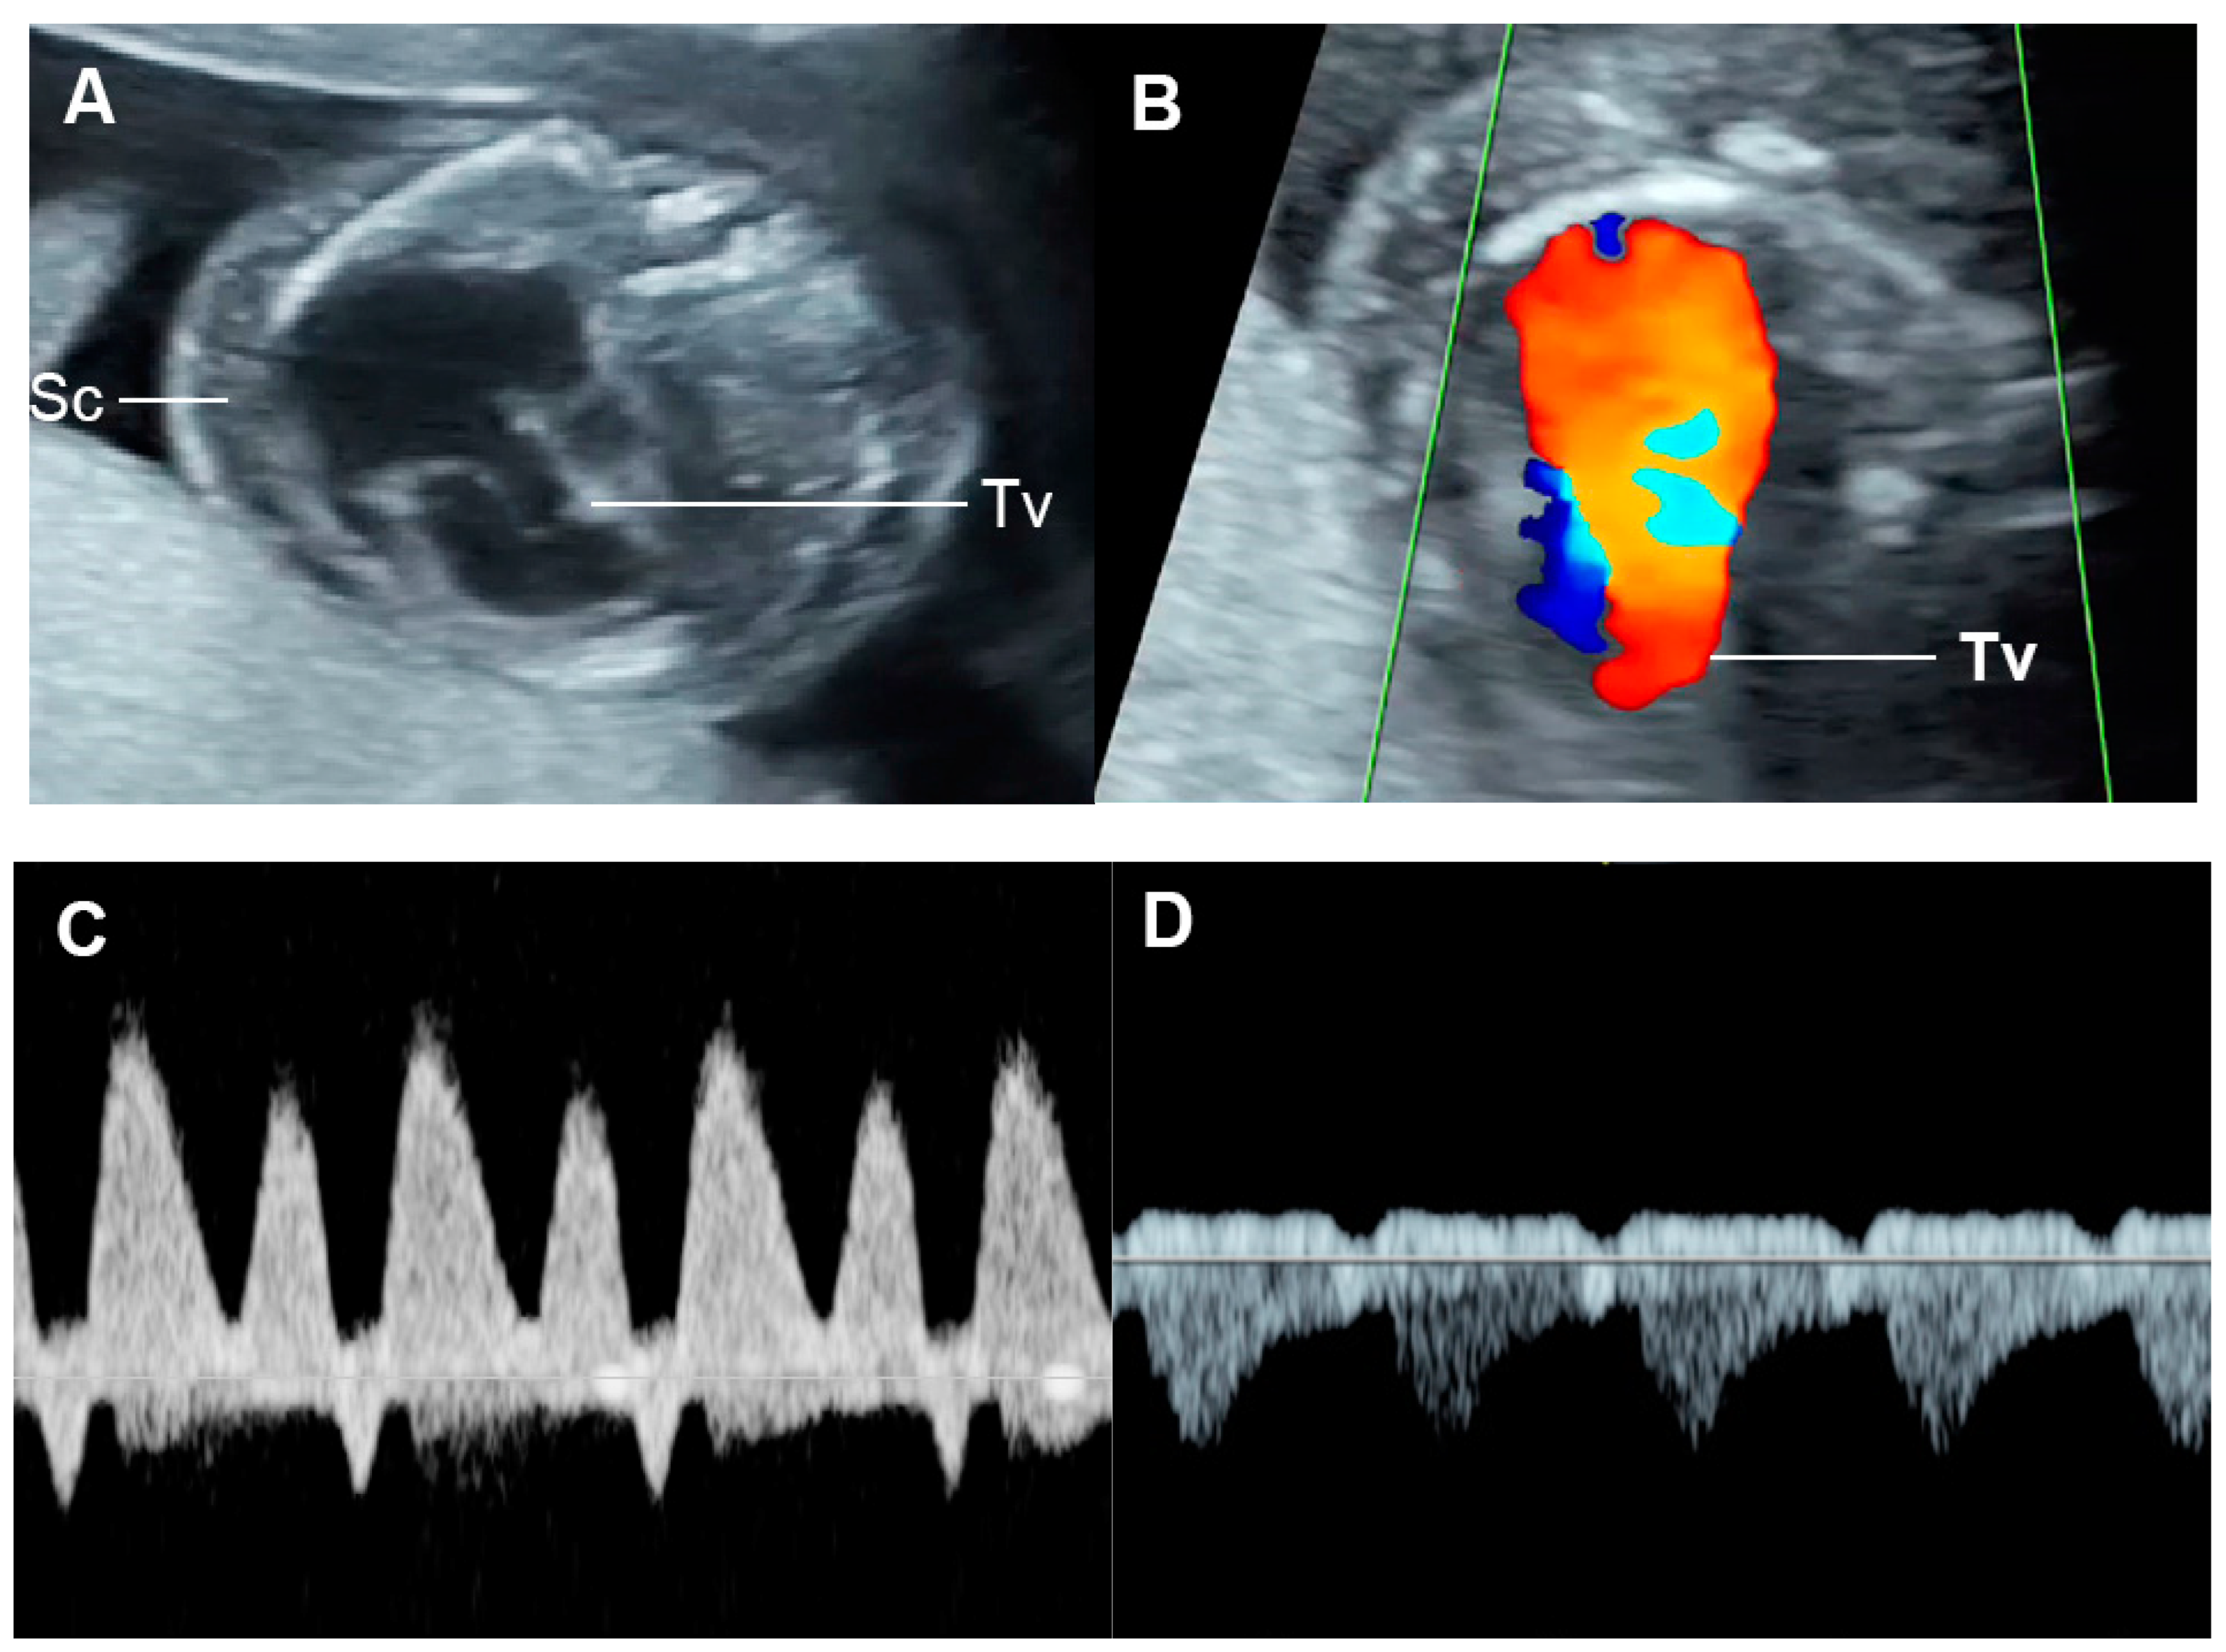

4.3. Fetal Valve Competency

| E/A ratio | Monophasic | Diastolic dysfunction |

| Decreased | Diastolic dysfunction | |

| Increased | Volume loading/External compression | |

| Cardiac function | Normal function | Holosystolic TR, or ventricular shortening fraction < 28% | Holosystolic MR or TR dP/dt < 400, or monophasic inflow |